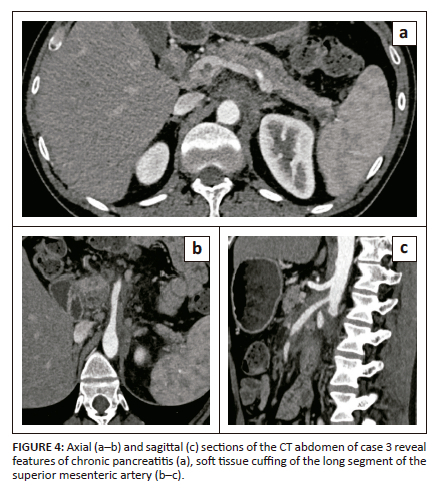

A 38-year-old male under evaluation for chronic pancreatitis was referred for CECT of the abdomen. The study revealed a mild reduction in the pancreatic bulk and an irregularly dilated main pancreatic duct (4.5 mm). It also revealed a cuff of non-enhancing soft tissue mass encircling the proximal 6.5 cm length of the superior mesentery artery with a maximal thickness of 10 mm, extending into the peripancreatic and/or pancreaticoduodenal groove (Figure 4a-c). The patient was evaluated for autoimmune disorders, but all tests were negative. The serum IgG4 levels were marginally raised (145 mg/dL). A diagnosis of IgG4-RD of the pancreas and superior mesenteric artery was made. The patient was commenced on steroid therapy and the symptoms gradually subsided.